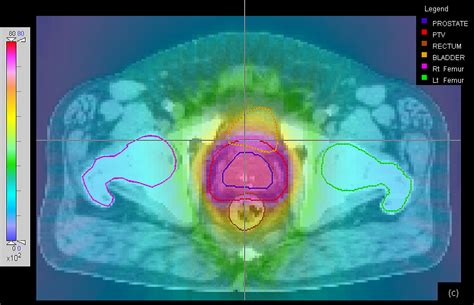

700×340

blogspot.com

External Radiation Therapy Prostate Cancer - All About Radiation